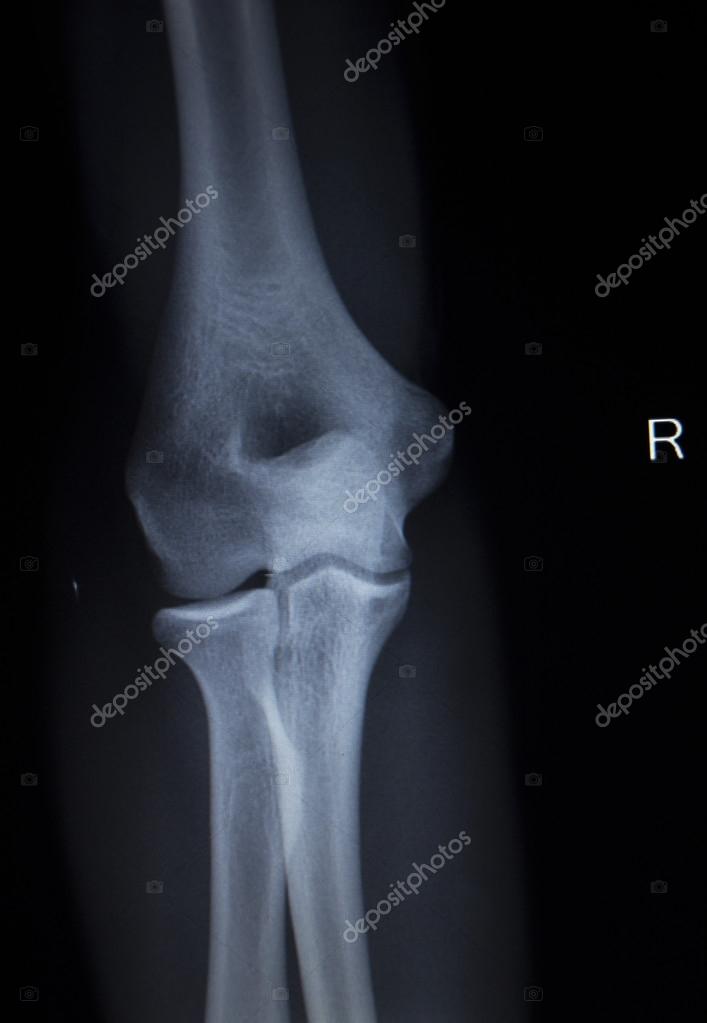

From depositphotos.com

Xray orthopedics Traumatology scan of elbow joint injury — Stock Photo Elbow Injury X Ray Fractures lines can be difficult to visualize after acute elbow injury, particularly in children. Below are eight sequential steps to aid in. The elbow series is a set of radiographs taken to investigate elbow joint pathology, often in the context of trauma. An elevated posterior fat pad is never normal, and a fracture or ligamentous injury must be suspected if. Elbow Injury X Ray.